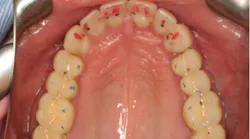

From the two-dimensional evaluation, the signs of occlusal instability were clear. Darren had very thin, chipping incisal edges, to the point where they were becoming transparent. The patient had almost worn shelves into the lingual of the maxillary anteriors, suggesting a restricted envelope of function. He also had wear into dentin in the anterior teeth as well as posterior teeth, and his anterior teeth had Class 1 mobility.

Esthetically, his maxillary incisal edges were slightly deficient vertically and needed to be lengthened, his length-to-width ratios needed to be improved, and his gingival contours were imbalanced. Darren had a slight cant with his occlusal plane, but he was not interested in correcting it. The mandibular incisal plane and arch form also required improvement. He was adamant that he wanted any esthetic changes to look natural and did not want “bright white” teeth.

Through working with Darren, we were able to provide the necessary treatment to obtain the five requirements of occlusal stability. He now has stable stops on all teeth, anterior guidance in harmony with the envelope of function, anterior teeth that provide immediate posterior disclusion in protrusive, and he no longer has working and balancing side excursive interferences.